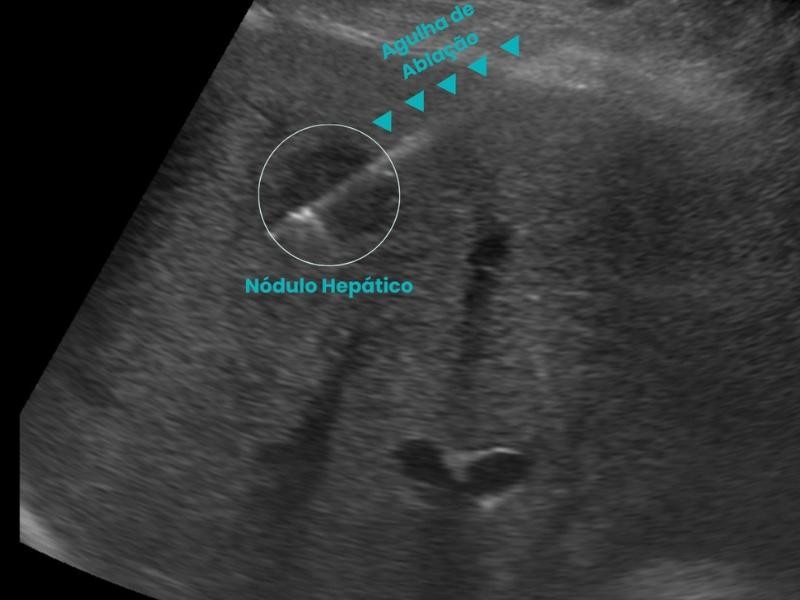

Conquistou o primeiro lugar no exame nacional da SOBRICE e se destaca em procedimentos minimamente invasivos, como ablação de tumores e biópsias guiadas. Atende nos melhores hospitais de São Paulo, incluindo o Hospital Nove de Julho e Vila Nova Star.